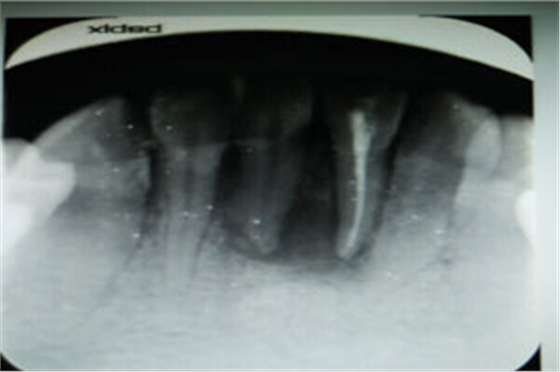

圖2.術(shù)前的根尖片影像、31根管治療已做,欠填少許。31、41根尖有橢圓形陰影,未見明顯骨白線。